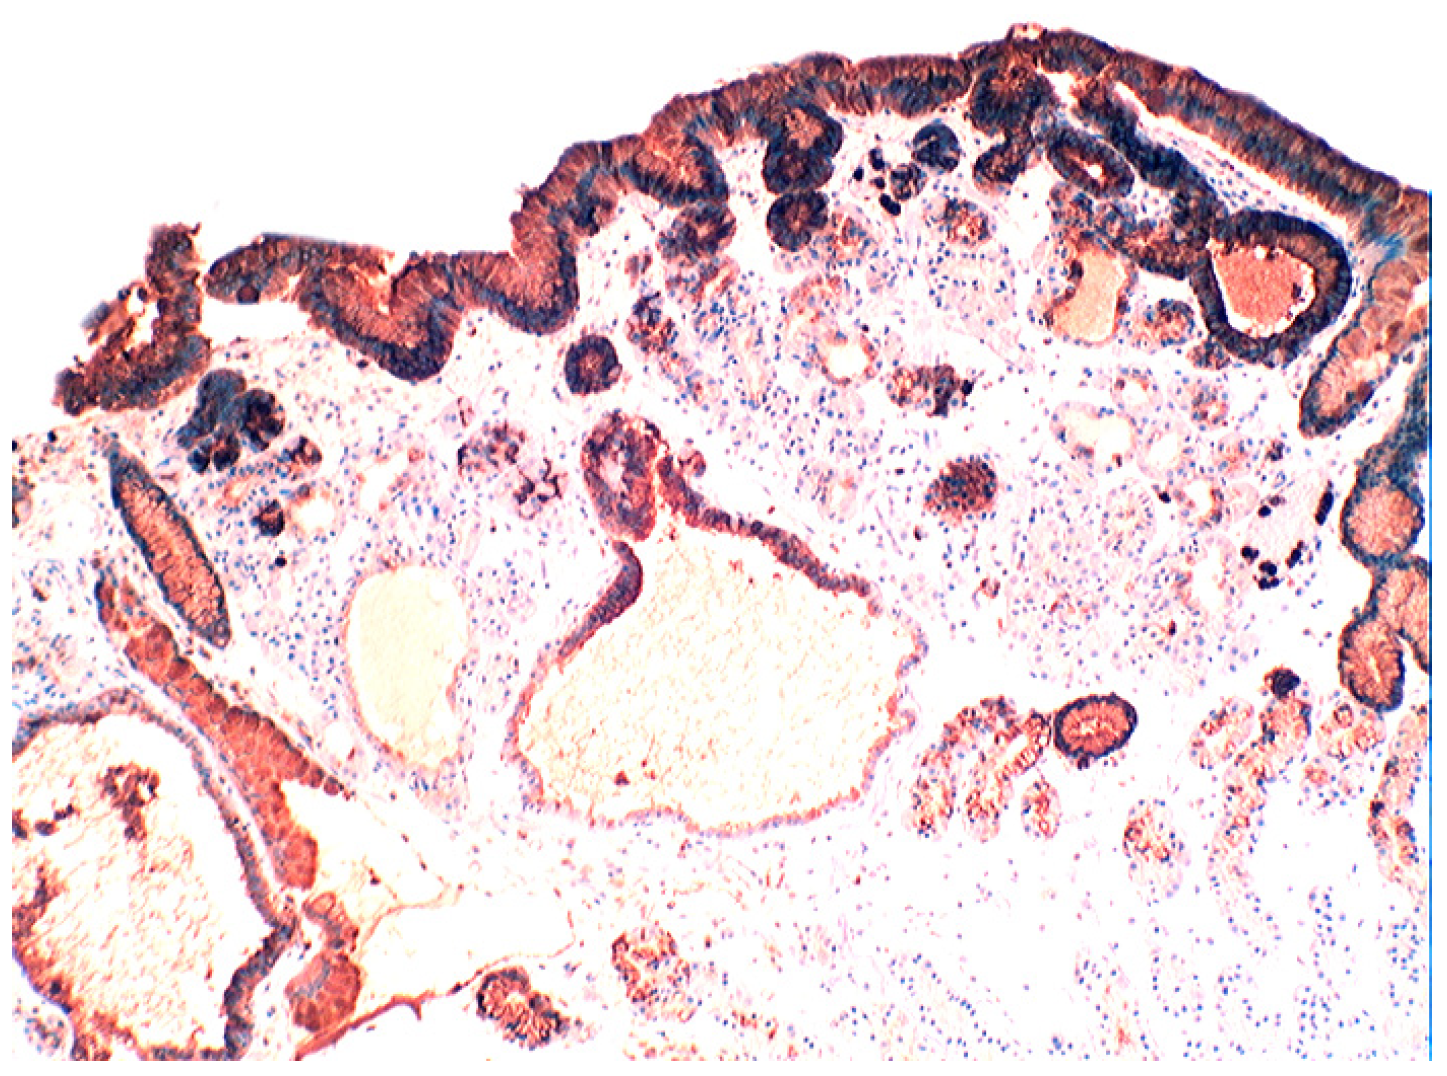

In the normal duodenal mucosa, Paneth cells produce lysozyme. In coeliac disease, lysozyme is up-regulated in goblet cells, in dilated crypts with mucus-metaplasia (Figure 9), a phenomenon more apparent in the bulbus [10] (Figure 10). It is not inconceivable that the lysozyme-rich mucus metaplasia mirror stem cell adaptation to the signals generated by the pathogenic bacteria present in the duodenal microenvironment [63].

Figure 10. Chronic atrophic duodenitis (celiac disease). Villous atrophy showing extensive lysozyme-rich mucus metaplasia of the crypts. Note absence of Paneth cells (lysozyme immunostain, ×10).